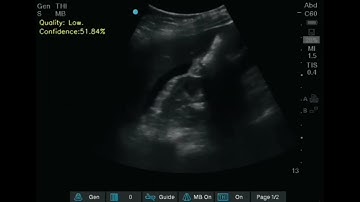

Introducing the First Ultrasound to Use Artificial Intelligence to Recognize Anatomy